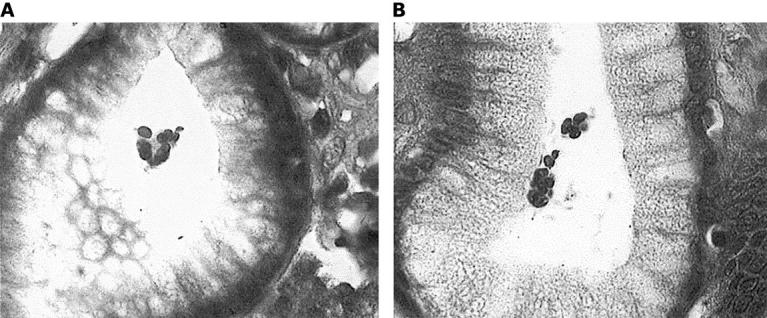

Figure 2 (A, B) Lymphocyte exudation into the lumen of gastric crypts in patient with Helicobacter heilmannii gastritis (original magnification, x1000).